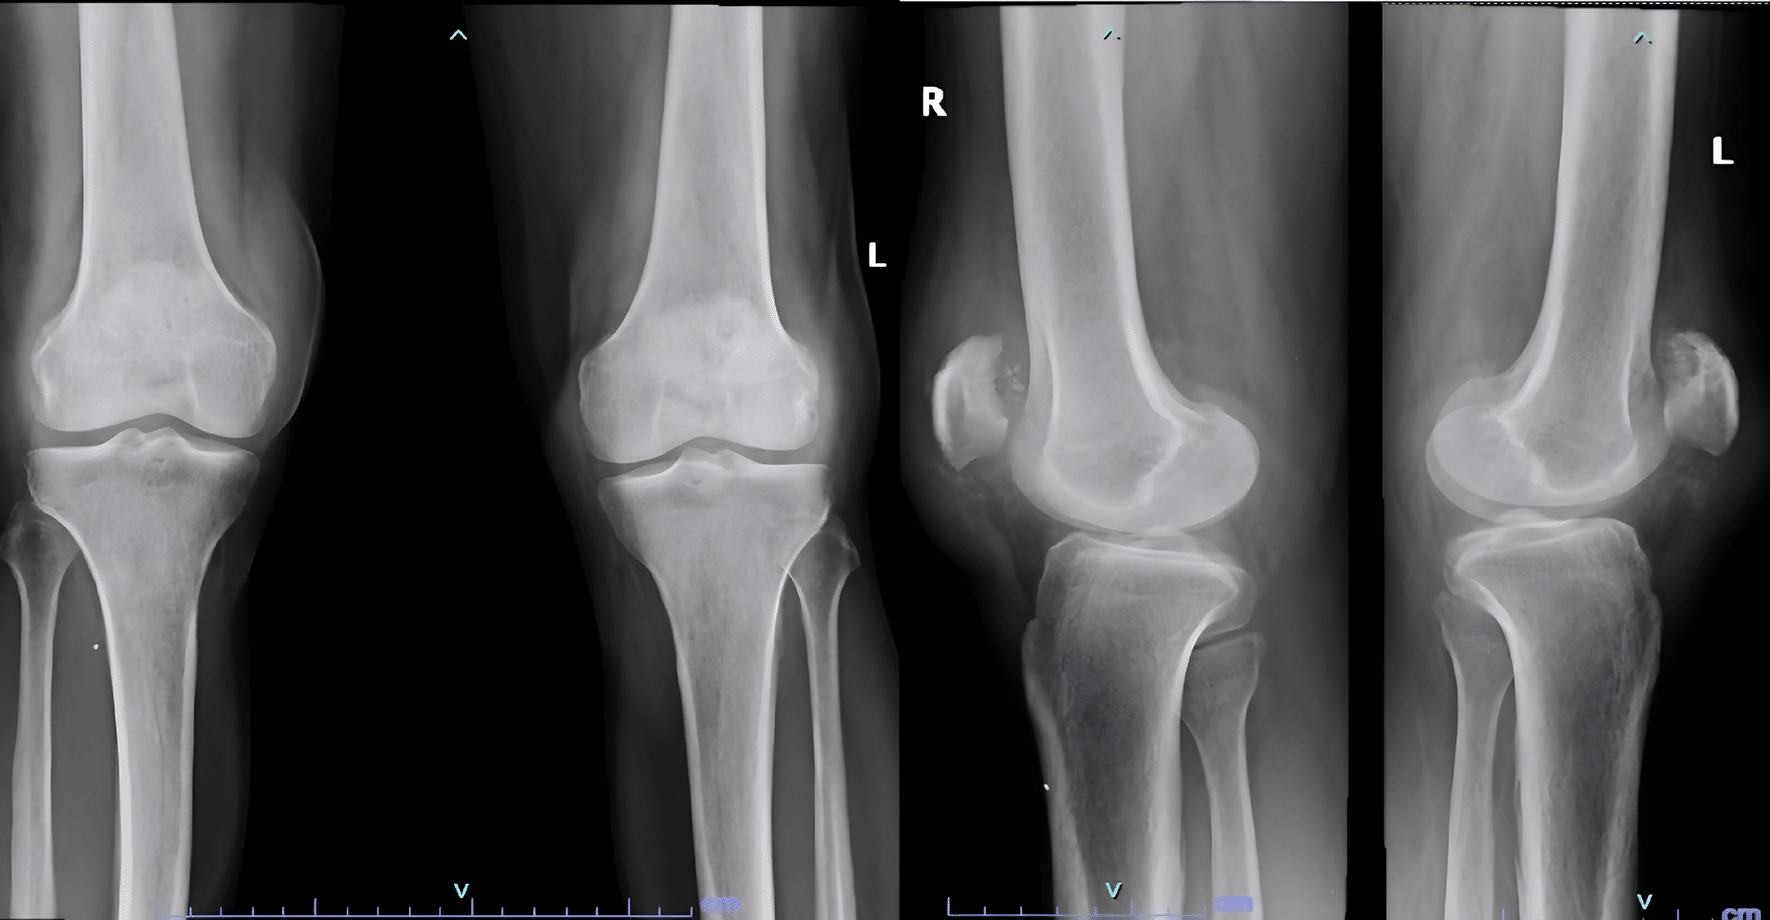

Examination revealed bilateral patella alta and boggy swelling in both knees with grade 0 power in bilateral knee extension. Imaging revealed isolated patella alta without any avulsed bony edges (Figure 5).

ba2523aa-b24d-4010-a34b-e26e289433e9_figure5.gif

Figure 5. Patella Alta noted in case 3 due to quadriceps rupture.

He was diagnosed with bilateral patellar tendon rupture and underwent open repair during which severe fraying of the tendons was noted (Figure 6). Robust repair was performed using non-absorbable sutures in a mattress pattern (Figure 7). He was given bilateral long knee immobilizers for 6 weeks to protect the repair, following which he was started on assisted ambulation with walker support over the next 4 weeks. At the final review at 6 months, he had grade 5/5 power in both his knee extensors with no appreciable lag on either side.